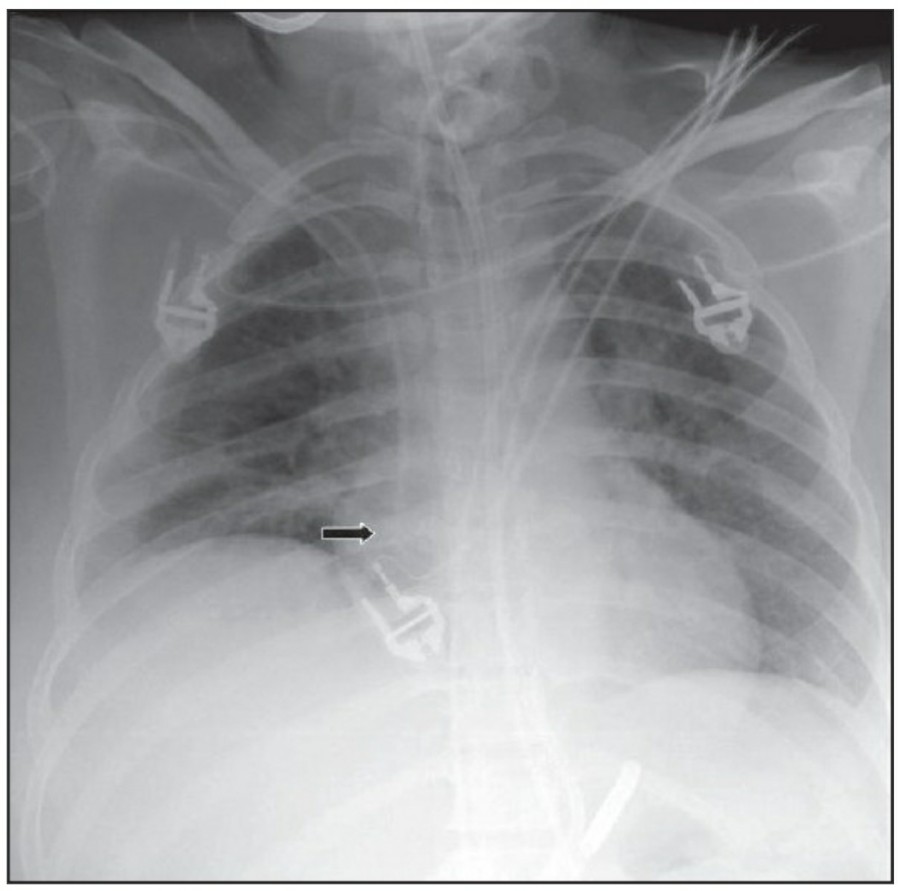

Pneumothorax

공기는 nondependent position으로 위치하므로, X ray상에서는 환자 자세에 따라 다르게 나타난다. Erect position에서 공기는 lung의 apicolateral surface에 위치하고 얇고 하얀 pleural line이 나타나며 그 뒤로 lung marking이 보이지 않는다.

하지만 pleural line 뒤로 lung marking이 존재한다고 해서 pneumothorax를 배제할 수 없다. Pneumothorax의 진단은 특히 parenchymal disease가 있을 때 진단하기 힘든데, 이는 compliance의 변화 때문에 collapse가 잘 안 되기 때문이다. Skin fold가 pneumothorax와 비슷하게 보이기도 한다.

중환자에서 pneumothorax의 진단은 종종 supine radiograph에서 내릴 수 있다. Supine position에서 공기는 anteromedial 방향으로 모이게 되는데, apical air collection이 있을 경우 large pneumothorax가 있음을 시사한다. 공기는 lung과 diaphragm 사이의 subpulmonic location에 trap 되어 있을 수도 있다. 공기가 costophrenic sulcus로 anterolateral extension 될 경우, 이 costophrenic sulcus의 radiolucency를 증가시키는데, 이를 deep sulcus sign이라고 한다. Subpulmonic pneumothorax의 다른 특징으로 diaphragm의 superior surface와 IVC 윗부분이 뚜렷하게 보일 수 있다.

중환자에서 tension pneumothorax의 진단은 매우 힘들다. ARDS와 같은 lung의 병리적인 기전이 lung compliance를 감소시킴으로써 total lumg collapse를 막는다. 또한 tension pneumothorax의 특징인 mediastinal shift가 PEEP으로 인해 나타나지 않을 수 있다. Chest X ray 상에서 tension pneumothorax는 hemidiaphragm의 depression이나 heart border, SVC, IVC의 이동으로 나타날 수 있다.